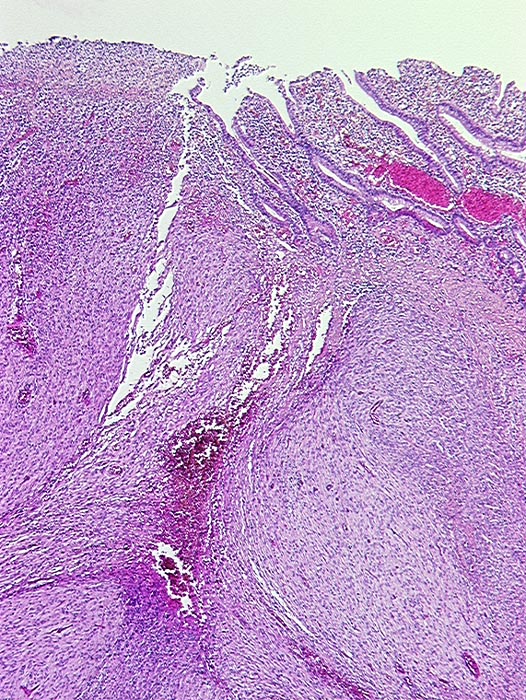

PathoPic ID 1086 - Ulzerierter gastrointestinaler Stromatumor (GIST)

Ulzerierter gastrointestinaler Stromatumor (GIST)

maligner Tumor

Dünndarm

Darm, Anus

Spindelzelliger von der Submukosa ausgehender Tumor. Links im Bild ist die Schleimhaut exulzeriert.

Metastasierender GIST. S-100 negativ, SM-Actin herdförmig positiv, CD 117 (c-kit) positiv.

Histologie